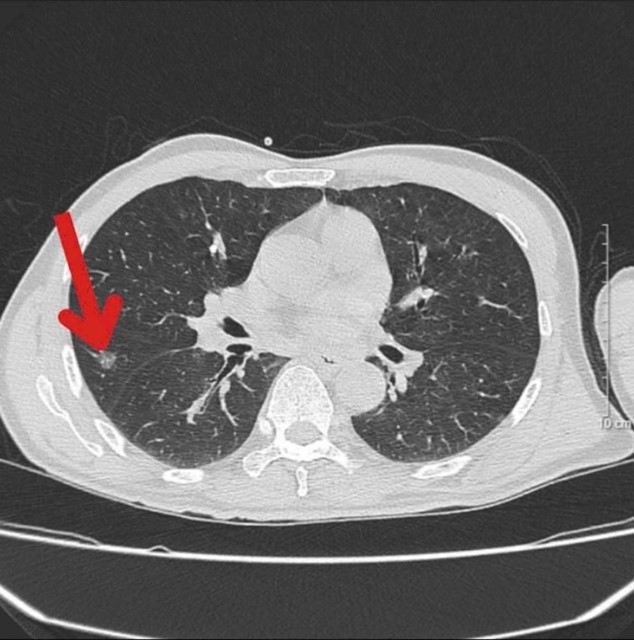

- Cắt lớp vi tính lồng ngực: Vài nốt kính mờ rải rác nhu mô phổi thuỳ trên phổi hai bên đường kính lớn nhất 6,5mm. Nốt bán đặc thuỳ giữa phổi phải đường kính 8,5mm. Nốt vôi hoá thuỳ trên phổi phải đường kính 6mm.

Hình 1. Hình ảnh chụp cắt lớp vi tính lồng ngực trước điều trị: Nốt bán đặc thuỳ giữa phổi phải đường kính 8,5mm (mũi tên)